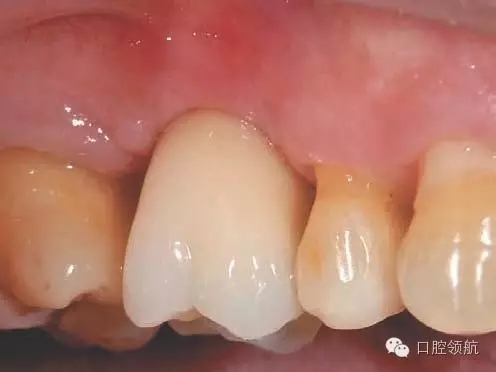

術(shù)后12周在獲得骨結(jié)合后,開始制作上部結(jié)構(gòu),術(shù)后16周戴入(圖8)。術(shù)后24周,CBCT影像顯示,種植體周圍有足夠的骨量(圖9)。

圖8 術(shù)后16周戴入上部修復體。